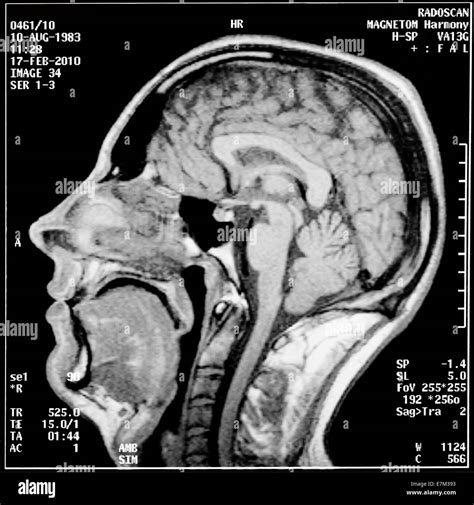

Se debe realizar una resonancia magnética nuclear (RMN) para descartar un tumor, otra anomalía estructural o esclerosis múltiple, ya que pueden provocar síntomas similares. Además, la resonancia magnética nuclear por lo general permite detectar el bucle anómalo en una arteria que está comprimiendo el nervio.